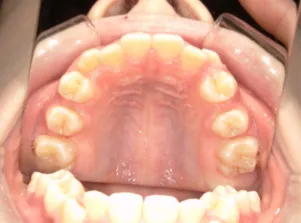

治療後⑤中2:治療終了

| 行ったご提案・診断内容 | 生え変わりが終わってなくマルチブラケット法による咬合治療には早い時期のため、顔立ちの成長を促す目的で歯列弓(アーチ)の拡大と前歯を並べながら永久歯が生えるのを待ち、咬合治療開始時に再診断で抜歯、非抜歯を最終検討する提案をしました。 再診断時(写真②)、歯列の拡大と上顎前歯の並べ替えはされていましたが八重歯となったため抜歯、非抜歯を検討しました。 口元は特に問題がなく非抜歯で八重歯を改善するためのスペースを作ることが可能なため非抜歯治療を提案しました。 治療は、 ・拡大および上顎左右6を遠心移動させてスペースを作る 予定装置 |